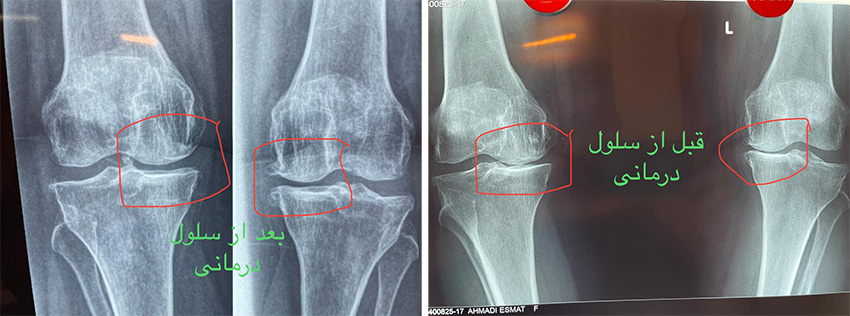

سلول درمانی زانو قبل و بعد